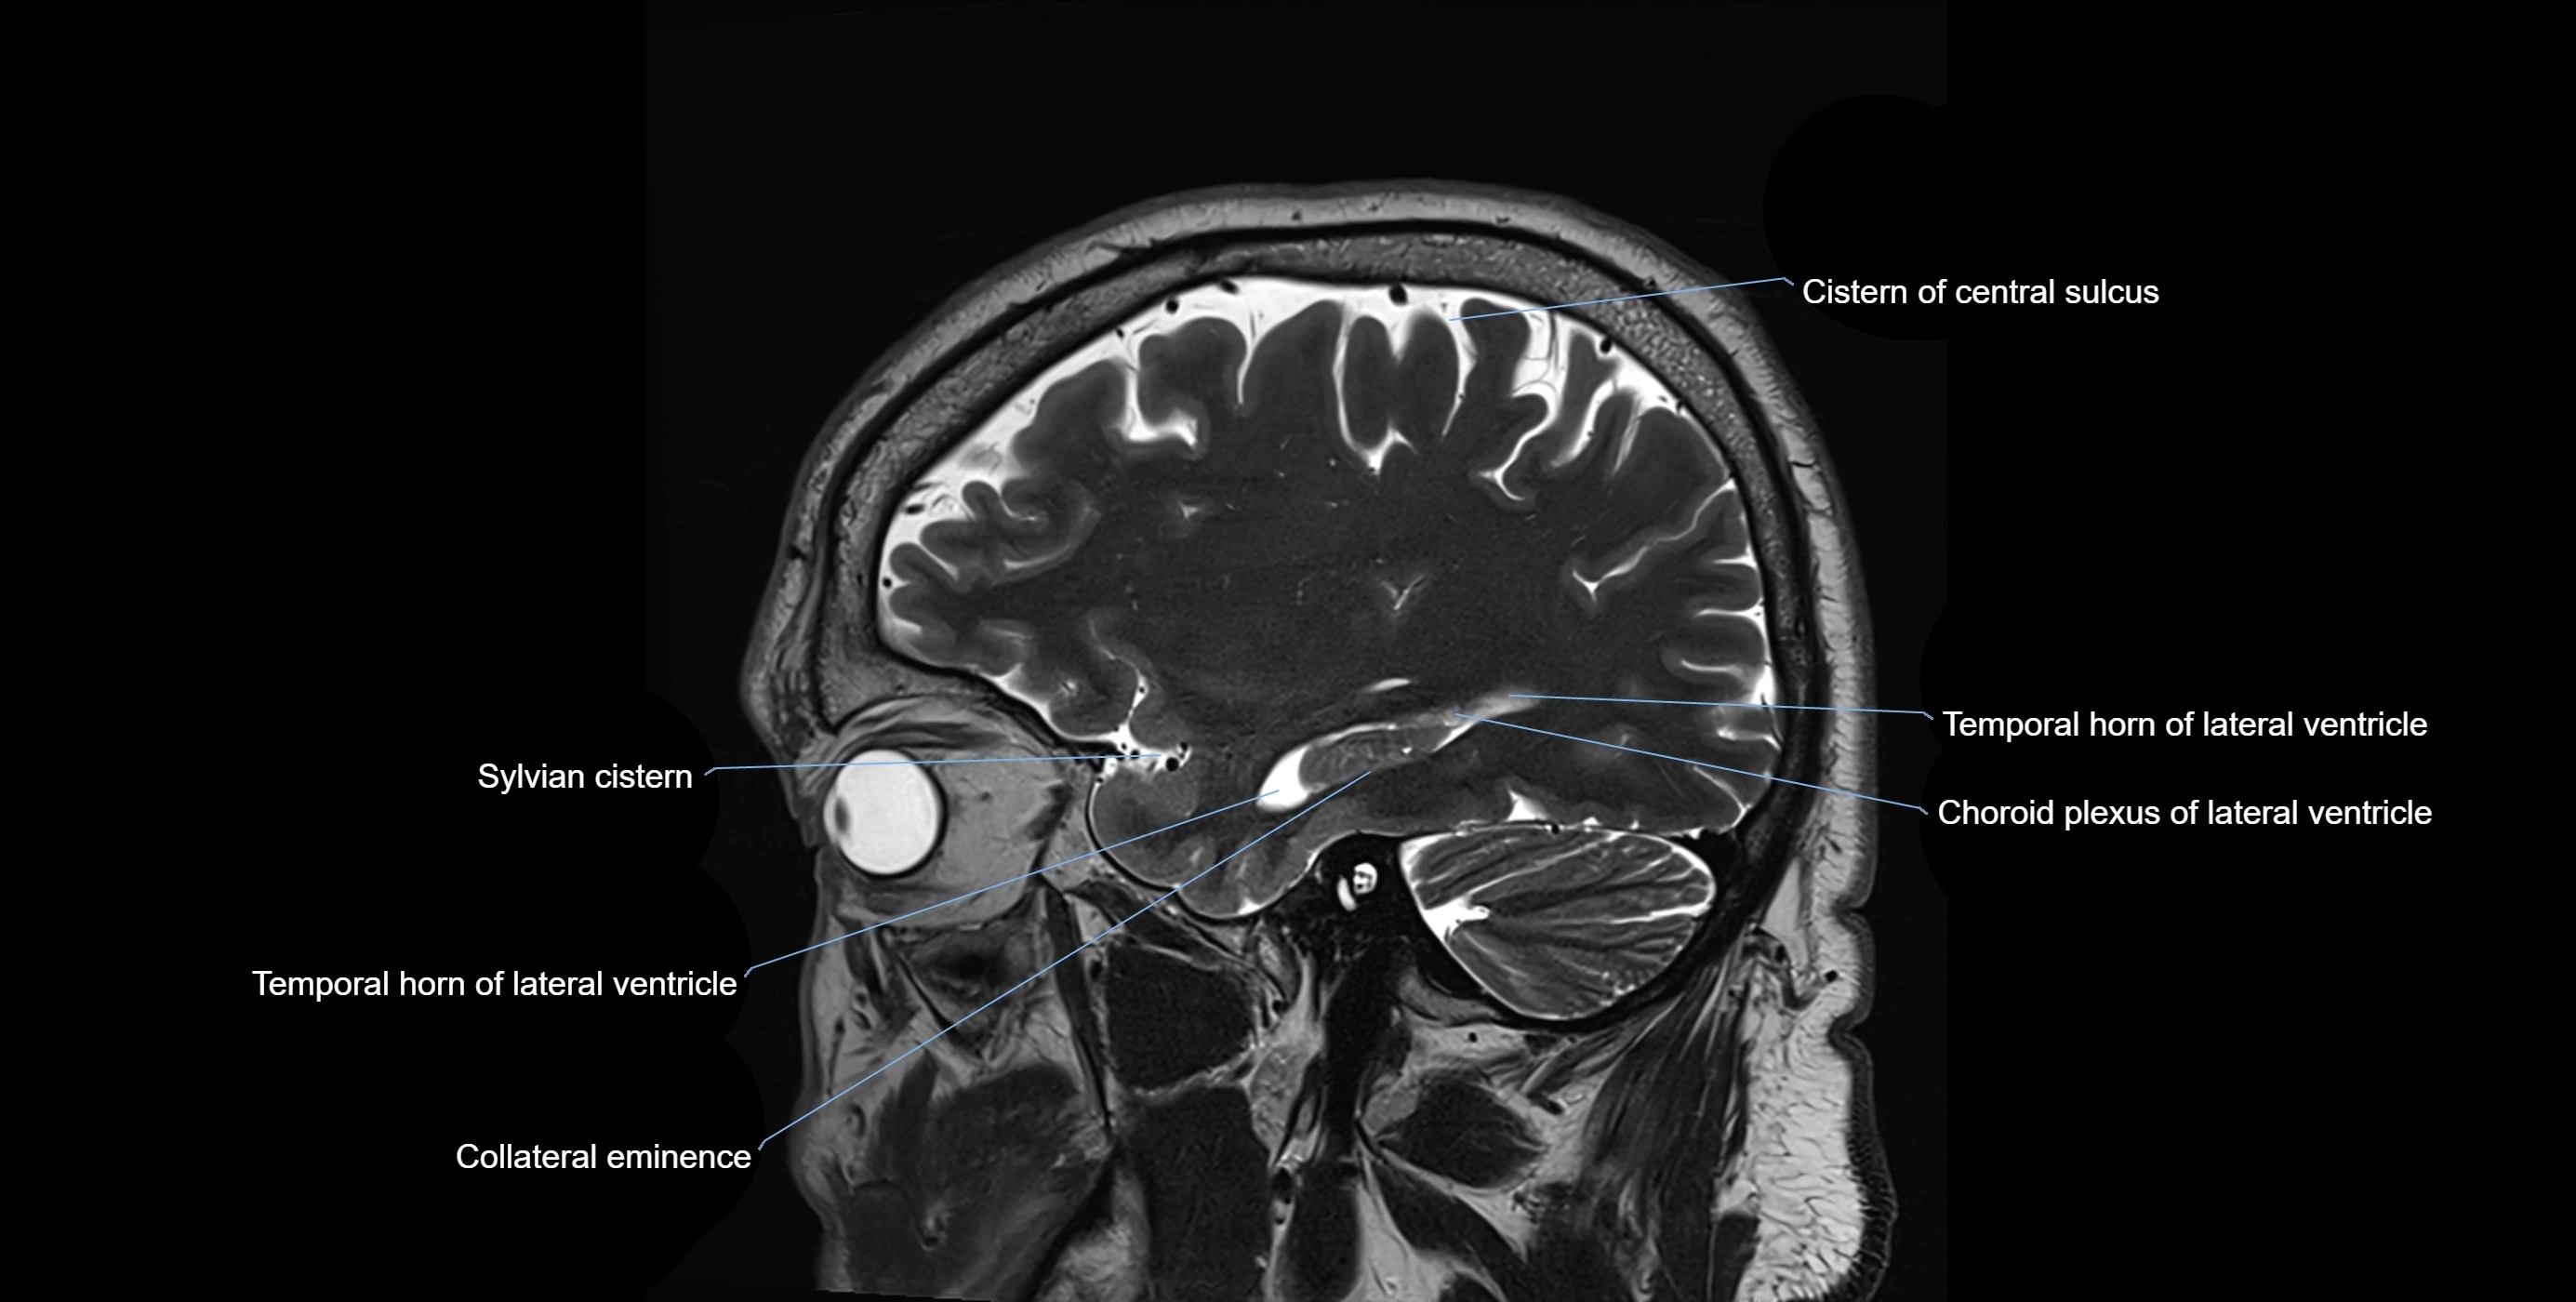

MRI images

image